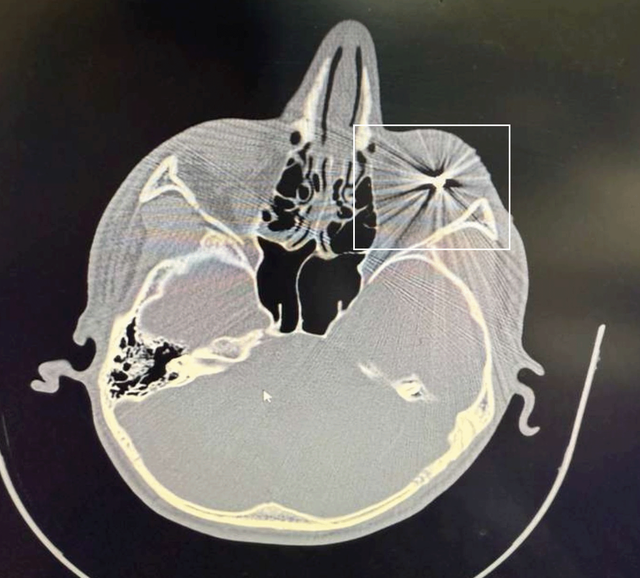

오른쪽 눈에 금속 알갱이가 박혀 있는 CT 사진

Obtained by BBC News Persian Forensic

BBC 페르시아어 서비스 포렌식팀이 단독 입수한 자료. 마슈하드 시위 참가자의 오른쪽 눈에 금속 알갱이가 박혀 있는 CT 사진

2022년 '여성, 삶, 자유'를 외치며 일어난 시위를 진압하는 과정에서 목격된 바와 같이, 올해 1월에도 산탄총이 광범위하게 사용되며 수많은 시위참가자가 목숨을 잃었으며, 수백명 혹은 수천 명이 영구적인 안구 손상을 입었다.

파라비 안과 병원의 병원장 가셈 파크라에이는 반관영 기관인 '이란 학생 통신사'에 1월 9~10일 사이에만 금속 탄환으로 인한 안구 파열로 응급 수술이 필요한 환자 약 1000명이 내원했다고 전했다.

BBC 페르시아어 서비스 포렌식팀은 마슈하드에서 시위에 참가했다가 부상당한여러 명의 CT 사진과 의료 기록을 입수했는데, 그중 한 CT 사진에는 안구 조직에 금속 물질이 박혀 있는 모습이 또렷하게 확인된다.